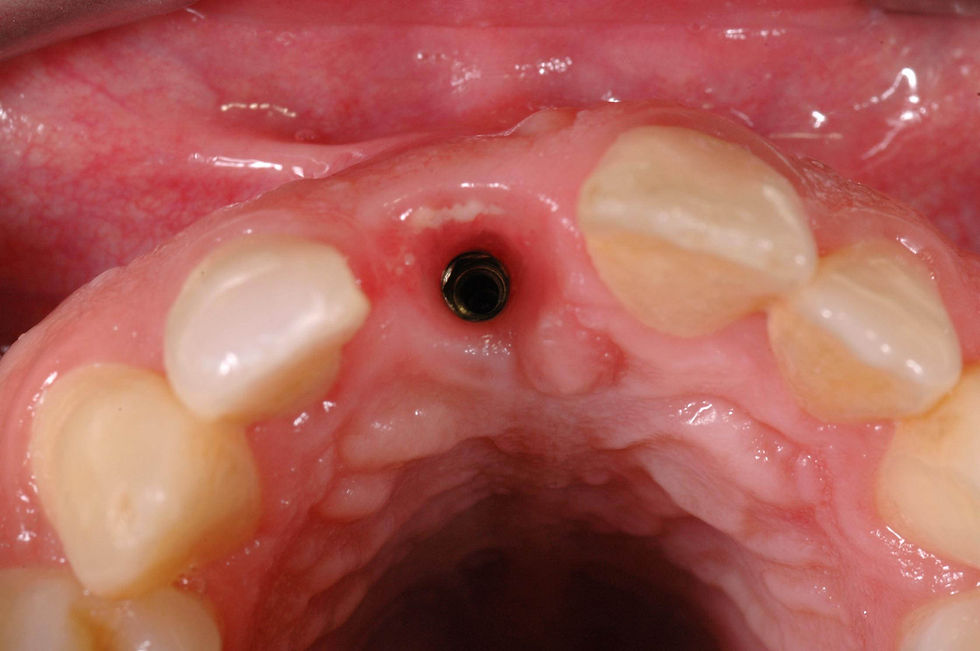

Occlusal view of the zirconia post in situ.

Detail of the healing of peri-implant tissues at the time of the definitive crown delivery: residues of particulate material incorporated in the vestibular soft tissues without clinical signs of inflammation confirm a favorable healing.